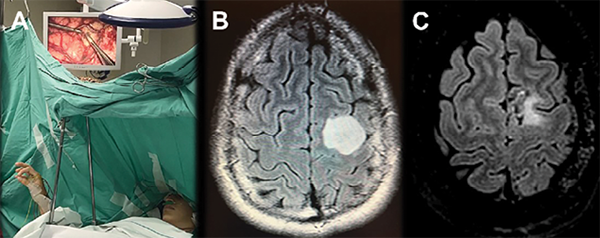

Figura 4. Ejemplo de caso de glioma de bajo grado en área de Broca (A-D). A. Vista en detalle de la posición del paciente en el quirófano y la disposición de los campos quirúrgicos durante craneotomía con paciente vigil y mapeo cortical. El posicionamiento debe realizarse previo a la inducción anestésica, con participación activa del paciente. B. Los campos estériles deben colocarse de manera tal que permitan una libre interacción entre el paciente y el neuropsicólogo, además de un adecuado manejo de la vía aérea. C y D. Documentación fotográfica intraquirúrgica previa y posterior a resección tumoral. La exéresis fue dirigida acorde a límites funcionales cortico-subcorticales, mediante mapeo cortical intraquirúrgico (cotonoides con referencia numérica: 1 y 3 corresponden a área motora de la mano; 4 y 5 evocaron un arresto del lenguaje bajo estimulación cortical). Se utilizó un loop vascular de silicona para delimitar el surco central. Se observa la cavidad de resección, con ausencia de márgenes entre límites funcionales por mapeo cortical y el tumor. El paciente presentó una disfasia de expresión leve postquirúrgica, la cual mejoró sustancialmente en un tiempo menor a 3 meses. Continúa actualmente realizando rehabilitación fonoaudiológica. Sc, Surco Central.

Figura 6. A. Ejercicio del área motora suplementaria y primaria (Tapping) en un tercer caso de una paciente femenina de 20 años, diestra, con diagnóstico de glioma de bajo grado en área premotora y motora primaria. La estimulación bloquea este ejercicio de coordinación. B. Cortes axiales de secuencia FLAIR de RMN prequirúrgica, en la cual se observa lesión glial de bajo grado hiperintensa en topografía de F1, F2 y giro precentral. C. Cortes axiales de secuencia FLAIR de RMN postquirúrgica, en la cual se observa pequeño remanente tumoral en F1 y giro precentral, debido a que la estimulación cortical en dichas áreas evocó una paresia del miembro superior derecho. La paciente evolucionó favorablemente, sin déficit motor, y retornó a una vida social y profesional normal, con una mejoría en su calidad de vida en comparación a las condiciones prequirúrgicas debido a convulsiones a repetición.